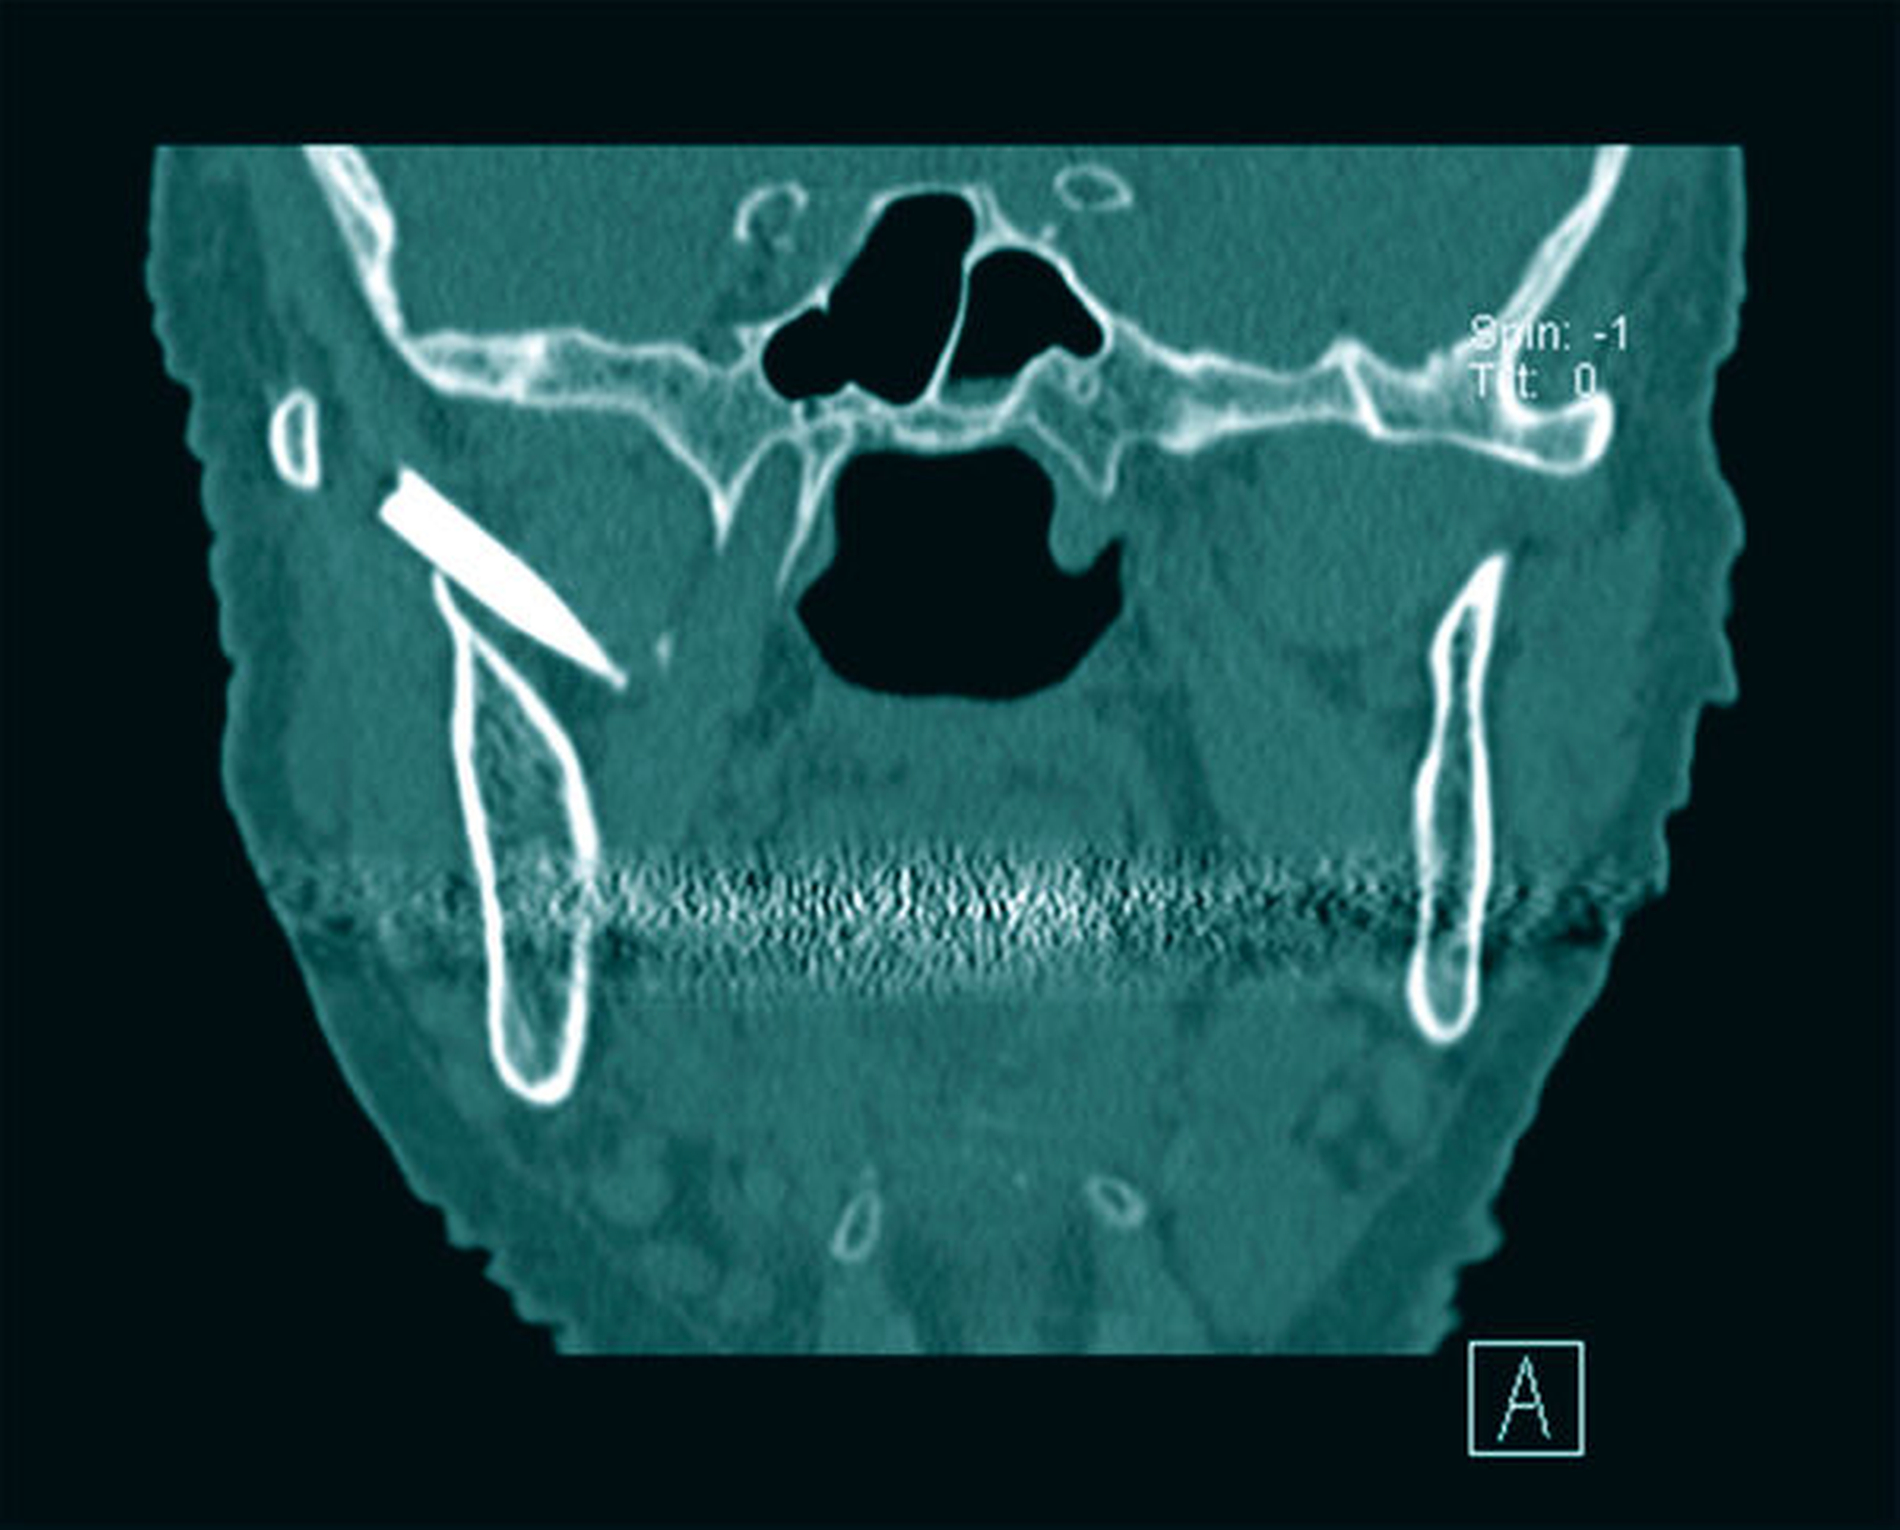

Auf der angefertigten Computertomografie war ein zur Geschichte der Patientin passendes Objekt in der Form einer Griffelspitze deutlich erkennbar, die im Spatium pterygomandibulare mit enger Lagebeziehung zum Nervus mandibularis lokalisiert war (Abbildungen 2 und 3).